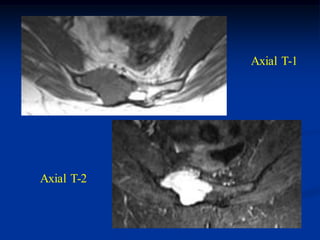

Case #608

17 year male with osteochondroma humerus

marrow

Axial T-1 MRI

cap

Sagittal T-1

MRI

Coronal T-2 MRI